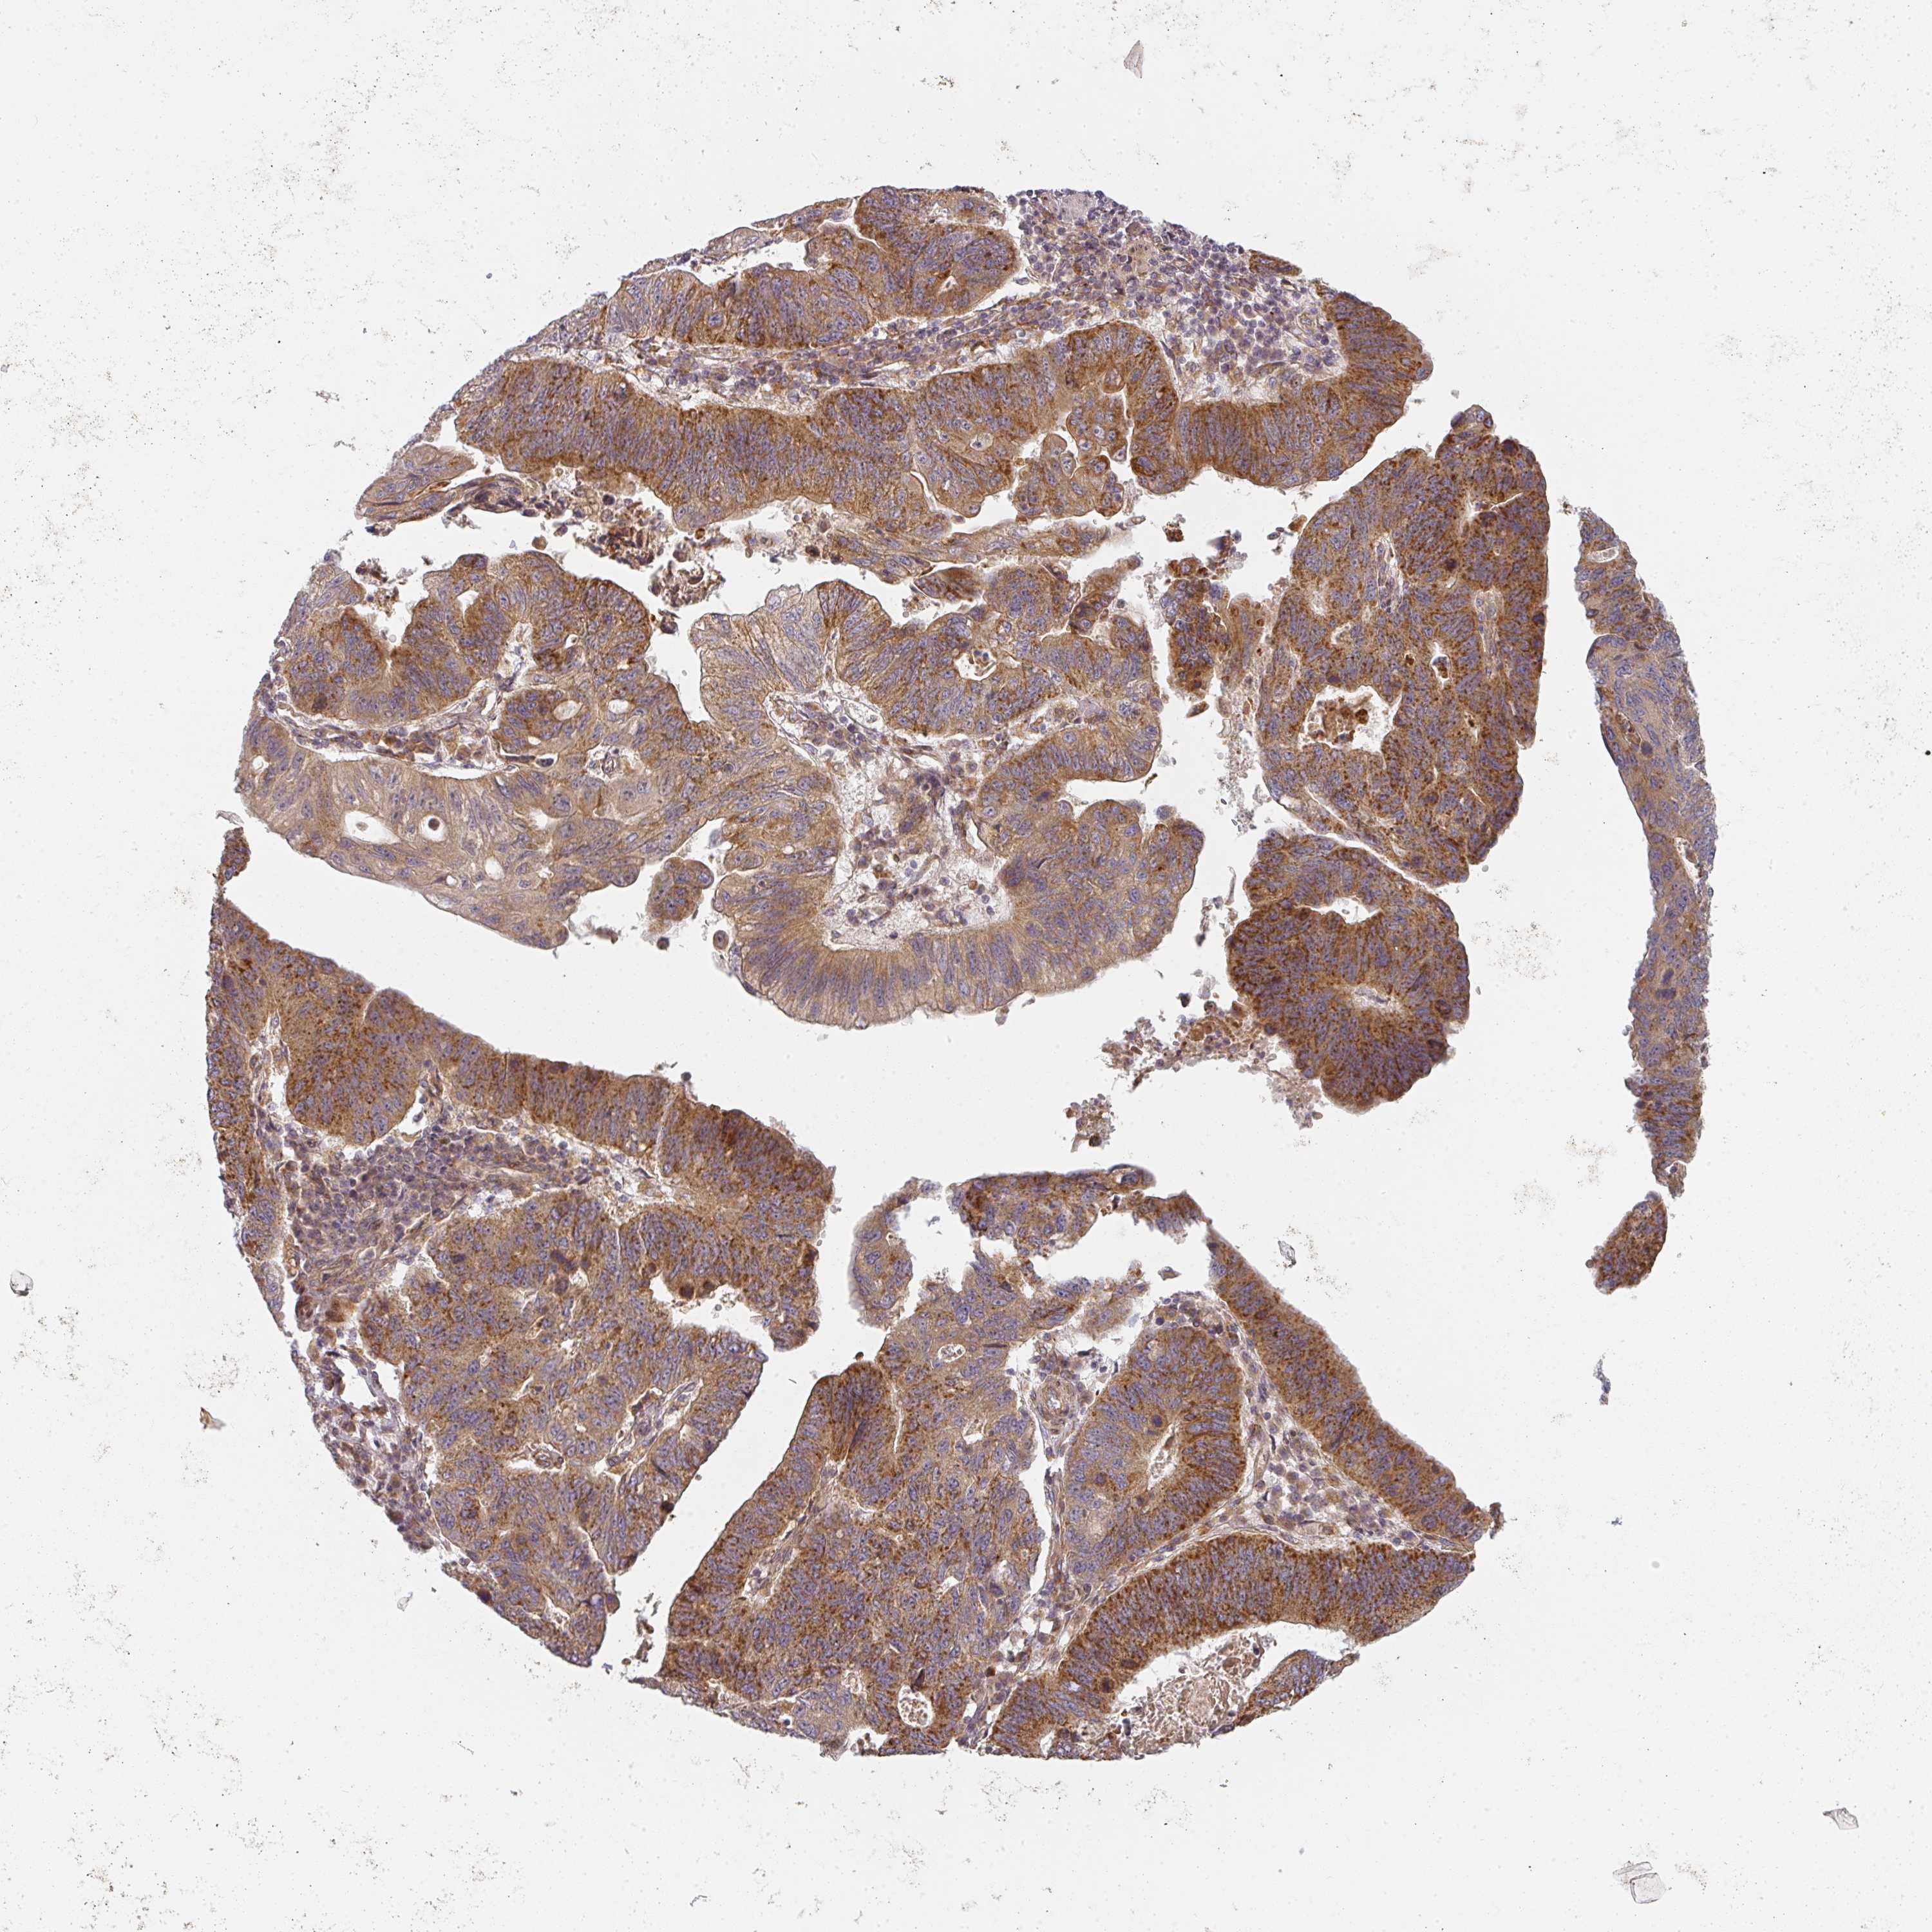

STOMACH CANCER - Protein expressioni

A mouse-over function shows sample information and annotation data. Click on an image to view it in a full screen mode. Samples can be filtered based on level of antibody staining by selecting one or several of the following categories: high, medium, low and not detected. The assay and annotation is described here.

Note that samples used for immunohistochemistry by the Human Protein Atlas do not correspond to samples in the TCGA dataset.

Antibody stainingi

Antibody staining in the annotated cell types in the current human tissue is reported as not detected, low, medium, or high, based on conventional immunohistochemistry profiling in selected tissues. This score is based on the combination of the staining intensity and fraction of stained cells.

Each image is clickable and will lead to virtual microscopy that enables deeper exploration of all samples and also displays staining intensity scores, fraction scores and subcellular localization as well as patient and tissue information for each sample.

Antibody HPA046577

Antibody HPA049664

Staining

High

Medium

Low

Not detected

Intensity

Strong

Moderate

Weak

Negative

Quantity

>75%

75%-25%

<25%

None

Location

Nuclear

Cytoplasmic/membranous

Cytoplasmic/membranous,nuclear

Adenocarcinoma, NOS

Adenocarcinoma, High grade